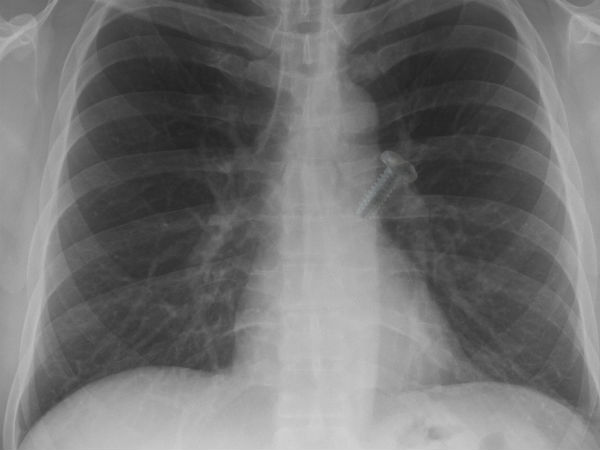

நுரையீரலை தாக்கும்

காசநோயால் பாதிக்கப்பட்டவர்களின் முறையற்ற இருமல், தும்மல் மற்றும் கண்ட இடங்களில் சளி துப்புதல் போன்றவற்றால், காற்றின் மூலம் மற்றவர்களுக்கும் அந்நோய் பரவுகிறது. நோய் எதிர்ப்பு திறன் குறைவாக உள்ள யாருக்கு வேண்டுமானாலும் காசநோய் வரலாம். முடி மற்றும் நகத்தை தவிர அனைத்து இடங்களையும் காசநோய் தாக்கும். குறிப்பாக, நுரையீரலை அதிகம் பாதிக்கிறது. காசநோய் பாதித்தவர்கள் 6 முதல் 8 மாதம் வரை மருந்து சாப்பிட்டால், முற்றிலும் குணப்படுத்தலாம்.

நுரையீரல் பாதிப்பு யாருக்கு?

தொண்டை மற்றும் நுரையீரலின் காரக கிரஹமான புதன் ஒரு ஜாதகத்தில் 6/8/12ம் பாவ தொடர்புகள், செவ்வாய், சனி, ராகு கேதுவுடன் சேர்ந்து பலமிழந்து நிற்பது போன்றவை ஜாதகருக்கு நிமோனியா காய்ச்சல் ஏற்படும் நிலையை ஏற்படுத்துகிறது. ஒருவருடைய ஜாதகத்தில் தொண்டை மற்றும் நுரையீரலை குறிக்கும் மிதுன ராசி 6/8/12 தொடர்புகள் பெறுவது, மிதுனத்தில் செவ்வாய், சனி, ராகு கேது போன்ற கிரஹங்கள் நின்று அசுபத்தன்மை பெறுவது.